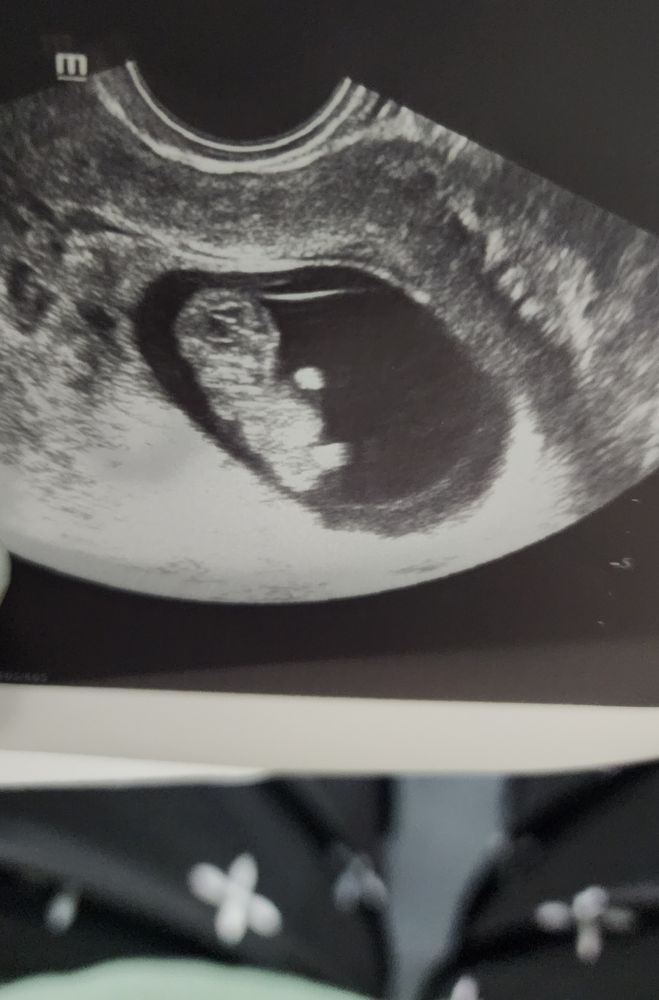

мой сладкий медвежонок🥰

Беременность прогрессирует, мой медвежонок(как назвала узистка😊) растет, нам уже 10 недель🤟 всем девочкам, кто хочет себе такое же счастье, тьфу-тьфу-тьфу на вас! Искренне желаю чтобы сбылось! 🫶 спасибо самым терпеливым, кто дочитал)))